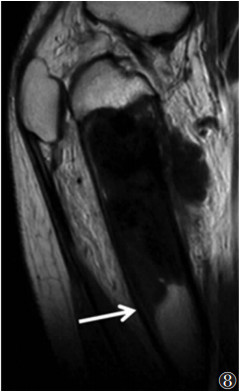

1.2.2 片状的长范围病变区域长范围呈片状而缺乏肿块感的边界不清的病变区域常提示炎性病变(图 7)。反之,骨恶性肿瘤突破骨皮质后可在周围软组织内形成边界清楚的实性肿块。恶性肿瘤,如骨肉瘤即使局限性在骨髓内也常被边界锐利的异常骨髓替代,特别是T1WI表现为边界清晰与正常骨髓区域截然分界(图 8),其机制有待进一步研究。

![]() |

| 图 8 男, 17岁, 骨肉瘤。MRI平扫T1WI显示股骨上部干骺端T1WI异常低信号区域, 边界清晰, 与正常骨髓截然分界(箭) |